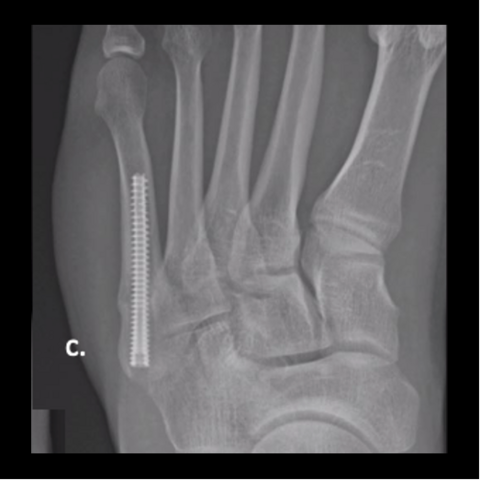

Figure 6c

Figure 6c. Plating of the fracture since screw fixation was not possible, and the patient refused external fixation for a second time.

Figure 6d

Figure 6d. Plating of the fracture since screw fixation was not possible, and the patient refused external fixation for a second time.

-

Figure 6e

Figure 6e. Plating of the fracture since screw fixation was not possible, and the patient refused external fixation for a second time.